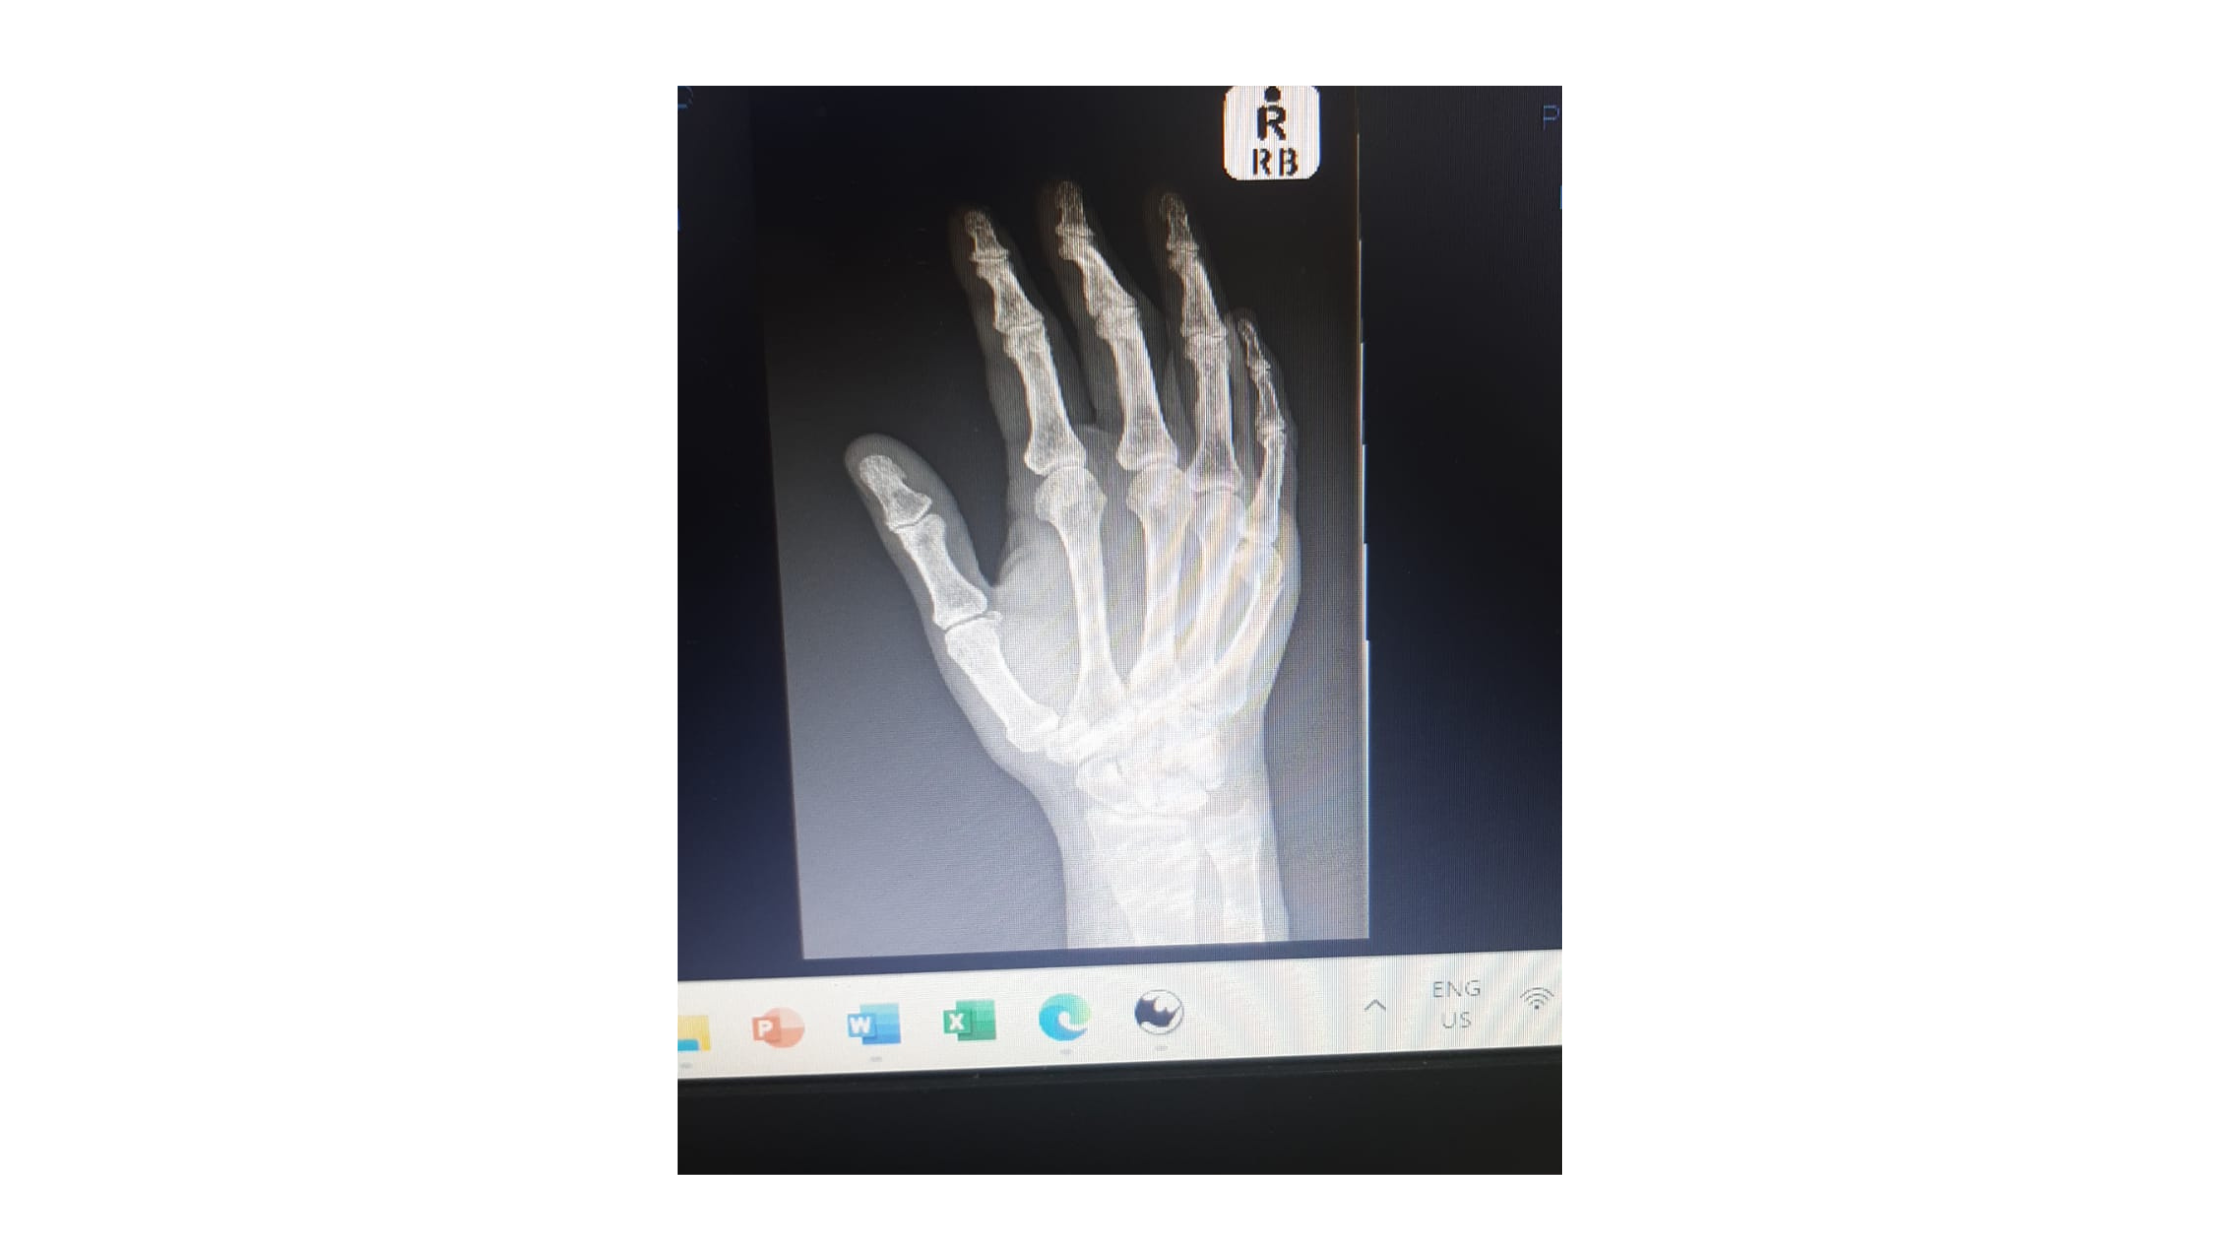

It is very rewarding to see people achieve independence again with our help. Our practice focuses specifically on upper limb- and hand therapy, spliniting, physical -, cognitive - & vocational rehabilitation and functional capacity evaluations.